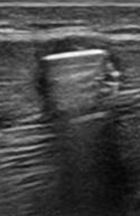

Identify this image.

Achilles tendon tear